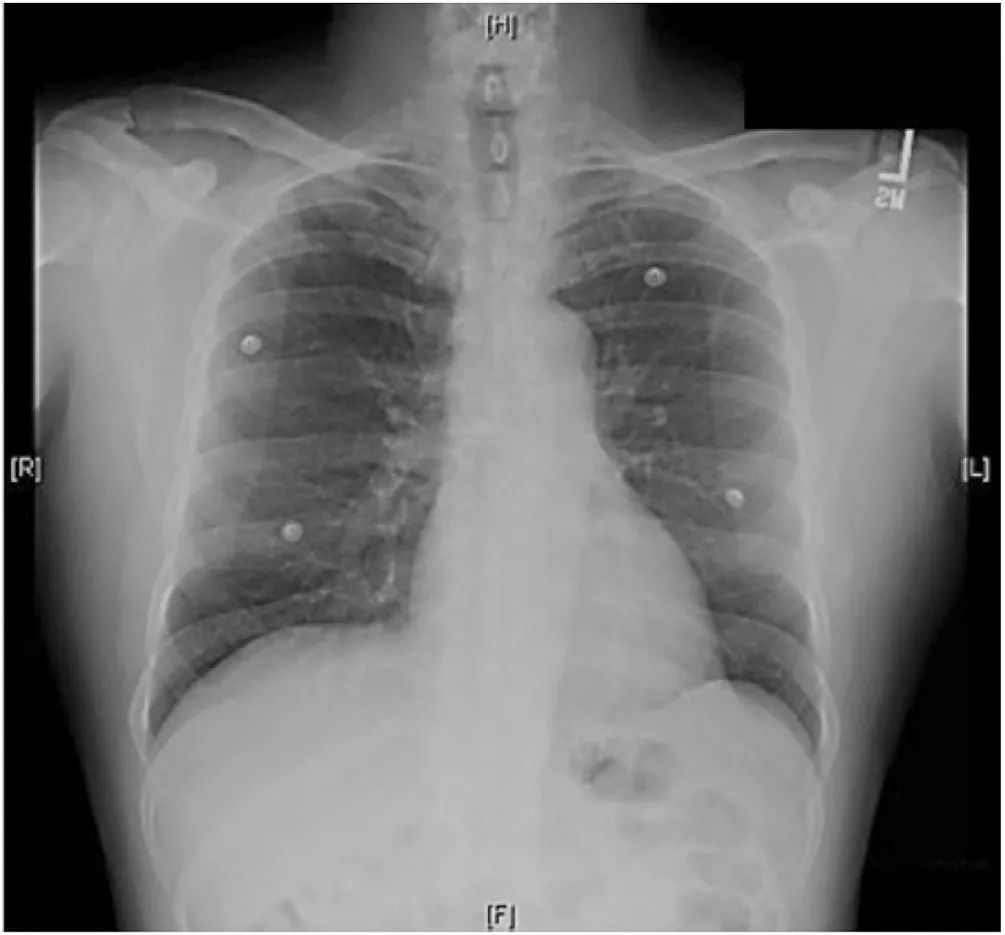

图1 胸片心影正常,无肺部疾病。

颅脑CT 示“左侧基底节区脑出血9 ml,右侧基底节区脑软化灶”。入院后查腹部增强CT 未见异常,无肿瘤,肾上腺形态及密度正常;胸片正常;双侧肾脏形态及肾脏血管超声正常;心脏彩超正常,主动脉弓未见异常,左室收缩功能良好,无反流及瓣膜改变;心电图可见左室高电压,多形室性早搏;尿常规蛋白2 ﹢,复查正常;电解质、肝肾功、心肌酶正常;CRP 16 mg /dl;ESR 22 mm/h;ASO、RF 阴性。眼底检查见Ⅰ°高血压眼底改变。